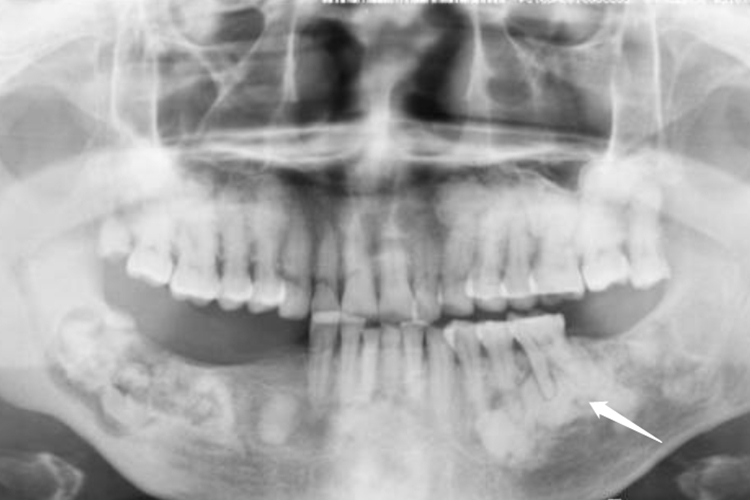

口腔致密性骨炎临床指根尖周致密性骨炎,X线检查显示患牙根尖区骨小梁增多、增粗,骨质密度增高,骨髓腔变窄甚至消失,与正常骨组织无明显分界。根尖部牙周膜间隙可增宽,根尖无增粗膨大。

根尖周致密性骨炎是因组织受到长期的轻微刺激,患者机体抵抗力较强,根尖部的牙槽骨不发生吸收性破坏,反而出现骨质的增生,围绕根尖周围形成一团致密骨。